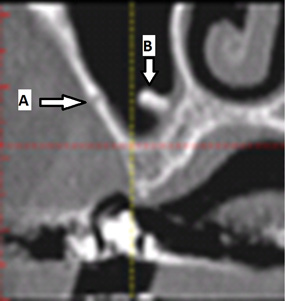

Fig 1. Mandibular foramen and lingula: cross-sectional view. A: The mandibular nerve enters the ramus at the mandibular foramen. B: The lingula is a ridge of bone superior to the mandibular foramen and provides attachment for the sphenomandibular ligament.

Figure 1